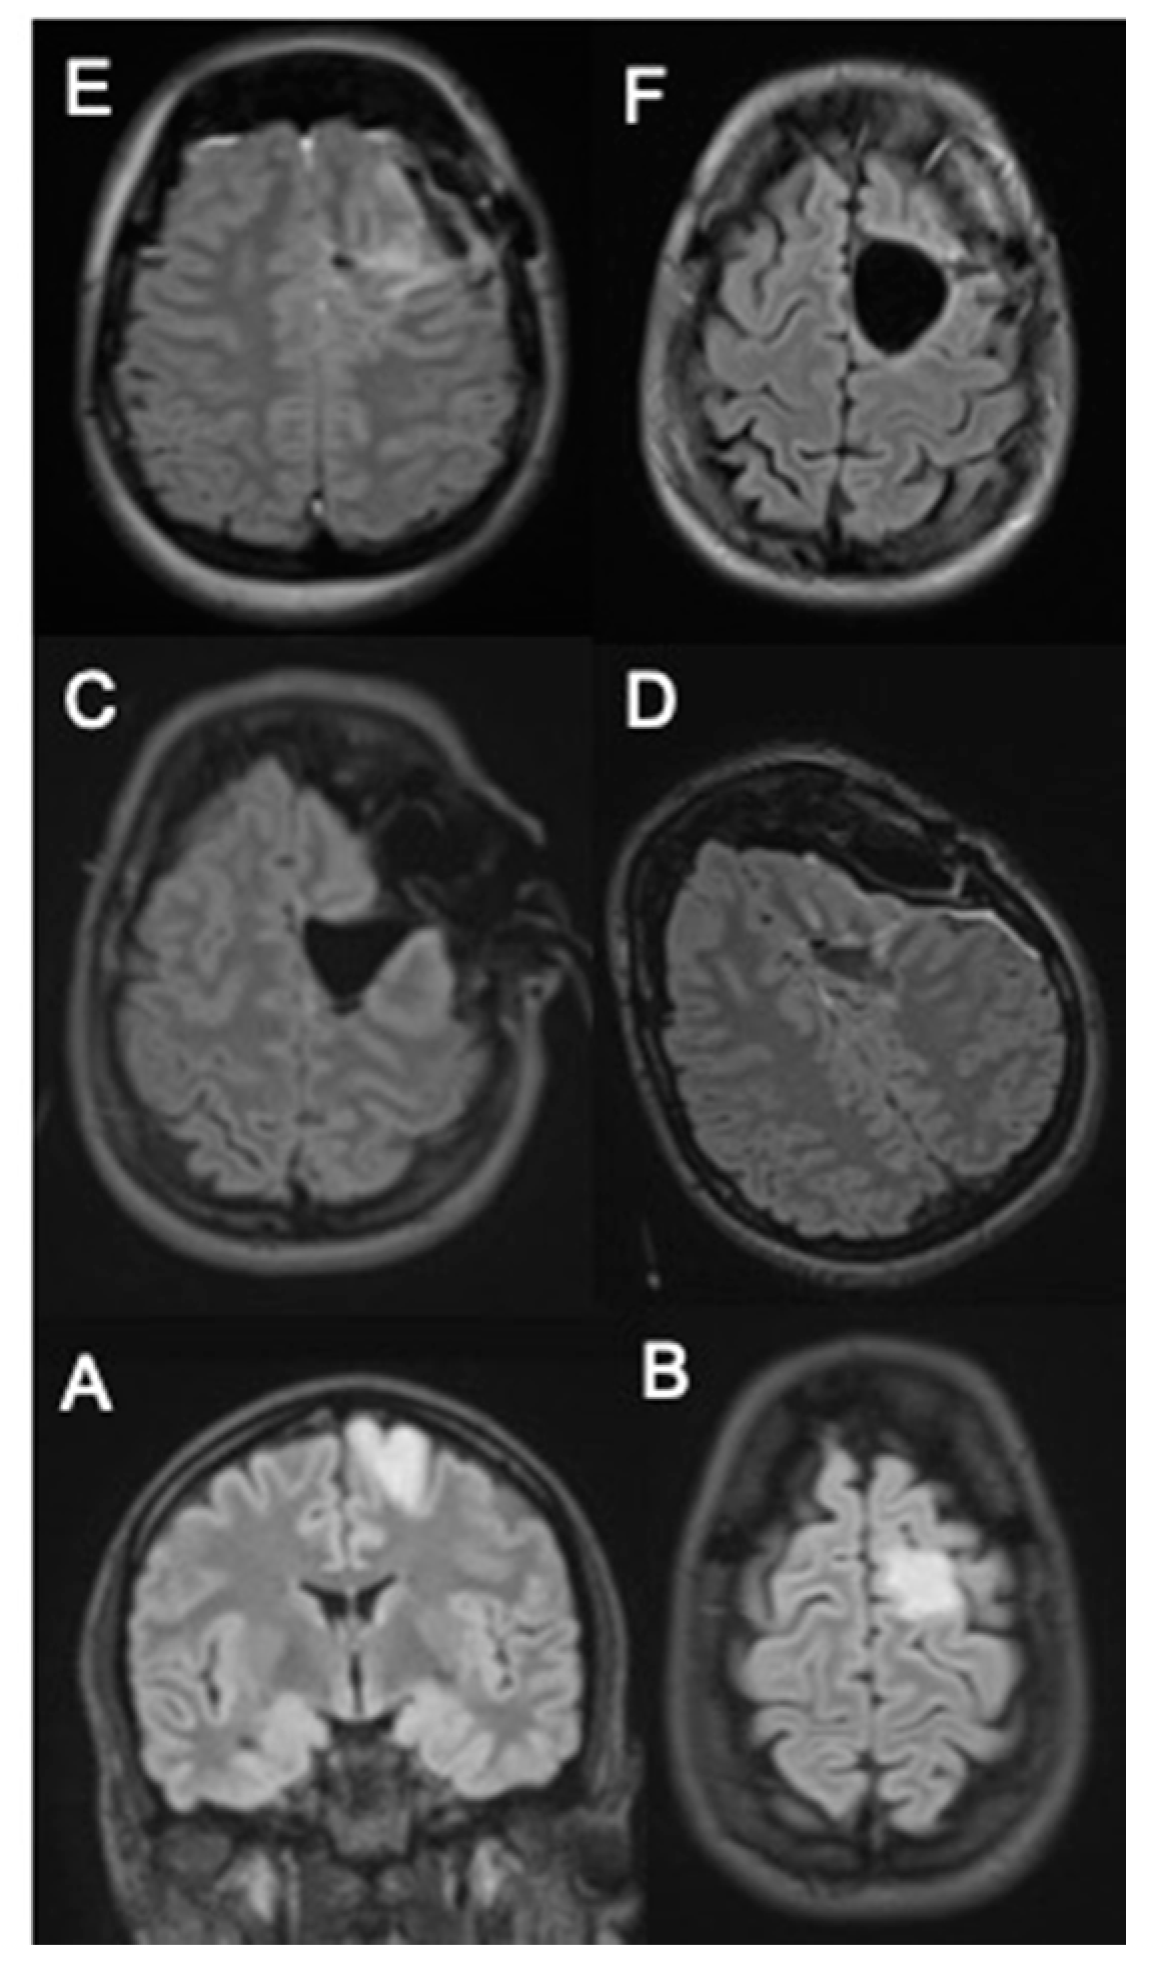

2.2. OR Setup and MRI

- Before surgery: T1 MPRAGE +/− Gadolinium enhancement, T2 SPACE, FLAIR 3D, DWI, PWI;

- Intraoperative MRI: T1 MPRAGE, T2 SPACE, FLAIR 3D, DWI, (+/− Gadolinium enhancement, PWI);

- Intraoperative after additional resection: T1 MPRAGE+/− Gadolinium enhancement, T2 SPACE, FLAIR 3D, DWI, PWI.

2.3. MRI Volumetric Assessment